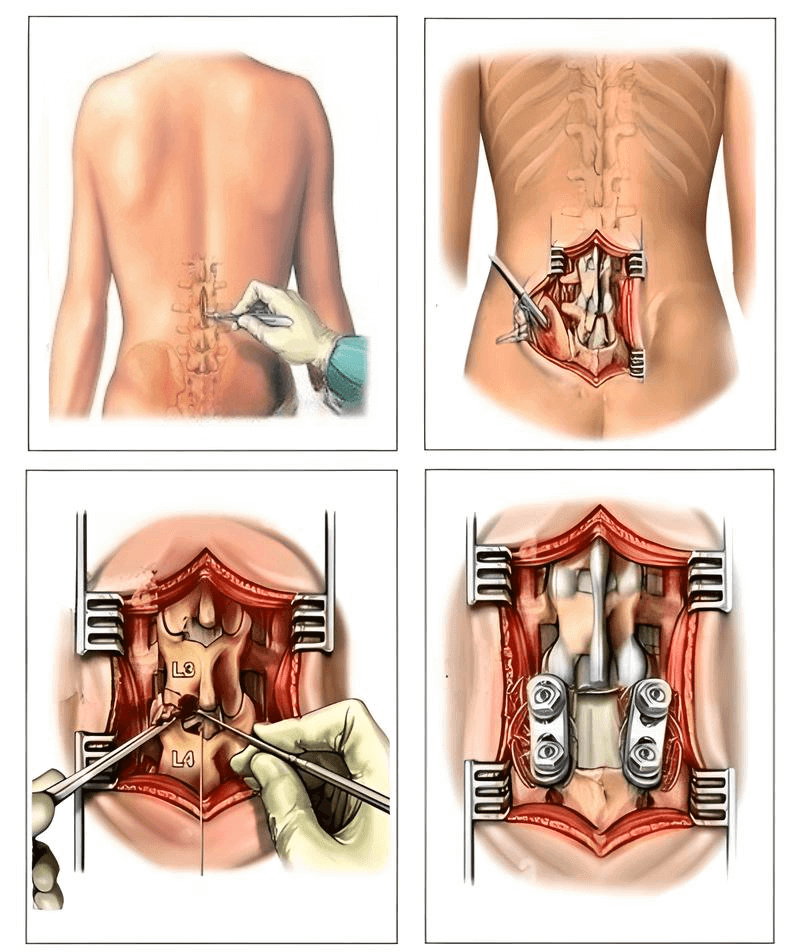

Una delle poche soluzioni che la medicina può offrire è un’operazione complicata e rischiosa per rimuovere l'ernia e inserire perni metallici! Ma pensateci bene! Anche i migliori chirurghi ammettono che un intervento sulla colonna vertebrale è una misura estremamente sconsigliata e pericolosa, CHE PORTA SPESSO A PROBLEMI ANCORA PIÙ GRAVI, INFEZIONI, CONTAGI, COMPLICAZIONI E PERSINO ALLA MORTE!

È importante notare che, in due terzi dei casi, l’ernia si ripresenta entro i 4 anni successivi alla rimozione, poiché la causa non viene eliminata!

E i pazienti dopo l’operazione, spesso, non perdono solo la salute, ma anche l’ultima speranza di una vita piena. Complicazioni, dolore cronico, mesi di riabilitazione — questo è solo l’inizio del vostro nuovo percorso infernale, pieno di sofferenze e limitazioni! Un percorso pieno di sofferenze e limitazioni!